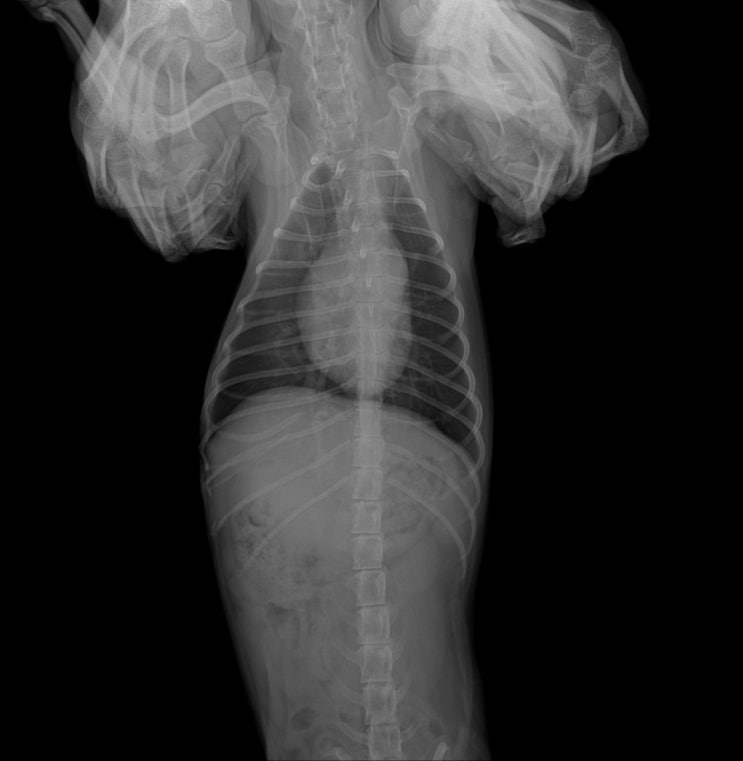

루비 신장수치,폐전이 엑스레이 상태 (24.4.13)

폐엑스레이는 3주전과 큰차이 없음. 기침이 심해 기관지염과 폐렴.감기 의심 했으나 엑스레이상 큰차이 없...